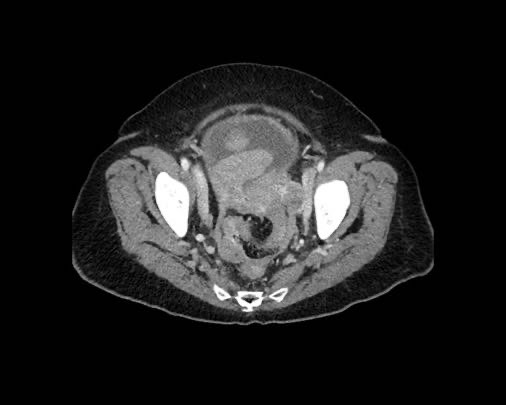

Cuộn xem ảnh CT

Ca lâm sàng 1

Cuộn qua các lát cắt.

Bạn có thể phát hiện tất cả các tổn thương cấy ghép phúc mạc không?

Bệnh nhân này đã được phẫu thuật và toàn bộ phúc mạc được ghi nhận phủ kín bởi các tổn thương u dạng kê.